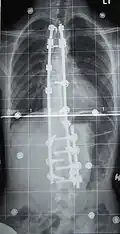

Beispiel einer langstreckigen Spondylodese mit vorderer und hinterer Fusion bei schwerer Skoliose